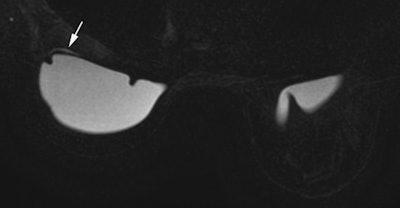

Ultrasound remains the gold standard for monitoring Poly Implant Prothese (PIP) breast implants, but new French data suggest that dedicated silicone sequences in MRI can help detect problems, particularly if asymptomatic patients wish to keep their implants.

In research involving 270 implants removed at the IGR, MRI with dedicated silicone sequences was helpful in diagnosis of perspiration. In the 93 perspiring implants, 43 out of 49 ultrasound exams were normal, with six false positives for rupture. Sixteen MRI examinations were also performed on the 93 perspiring implants. Seven out of nine MRI exams showed perspiration because MRIs were acquired with silicone sequences; five out of seven MRI exams were normal, but these MRIs were acquired without silicone sequences.

Out of the 270 removed implants, there were 13 ruptures. Ultrasound was available for 12 of these, with six yielding normal imaging results and six abnormal. Only one MRI exam was available, and it was abnormal.

Where there are suspicious clinical symptoms but normal or equivocal ultrasound results, MRI may be used as a second line investigative tool. Access to MRI is problematic for French patients because there are proportionally fewer MRI units in France than in neighboring countries, such as Spain, Italy, and Belgium. A request for its inclusion in diagnosis depends largely on the discretion of the individual surgeon or clinician.